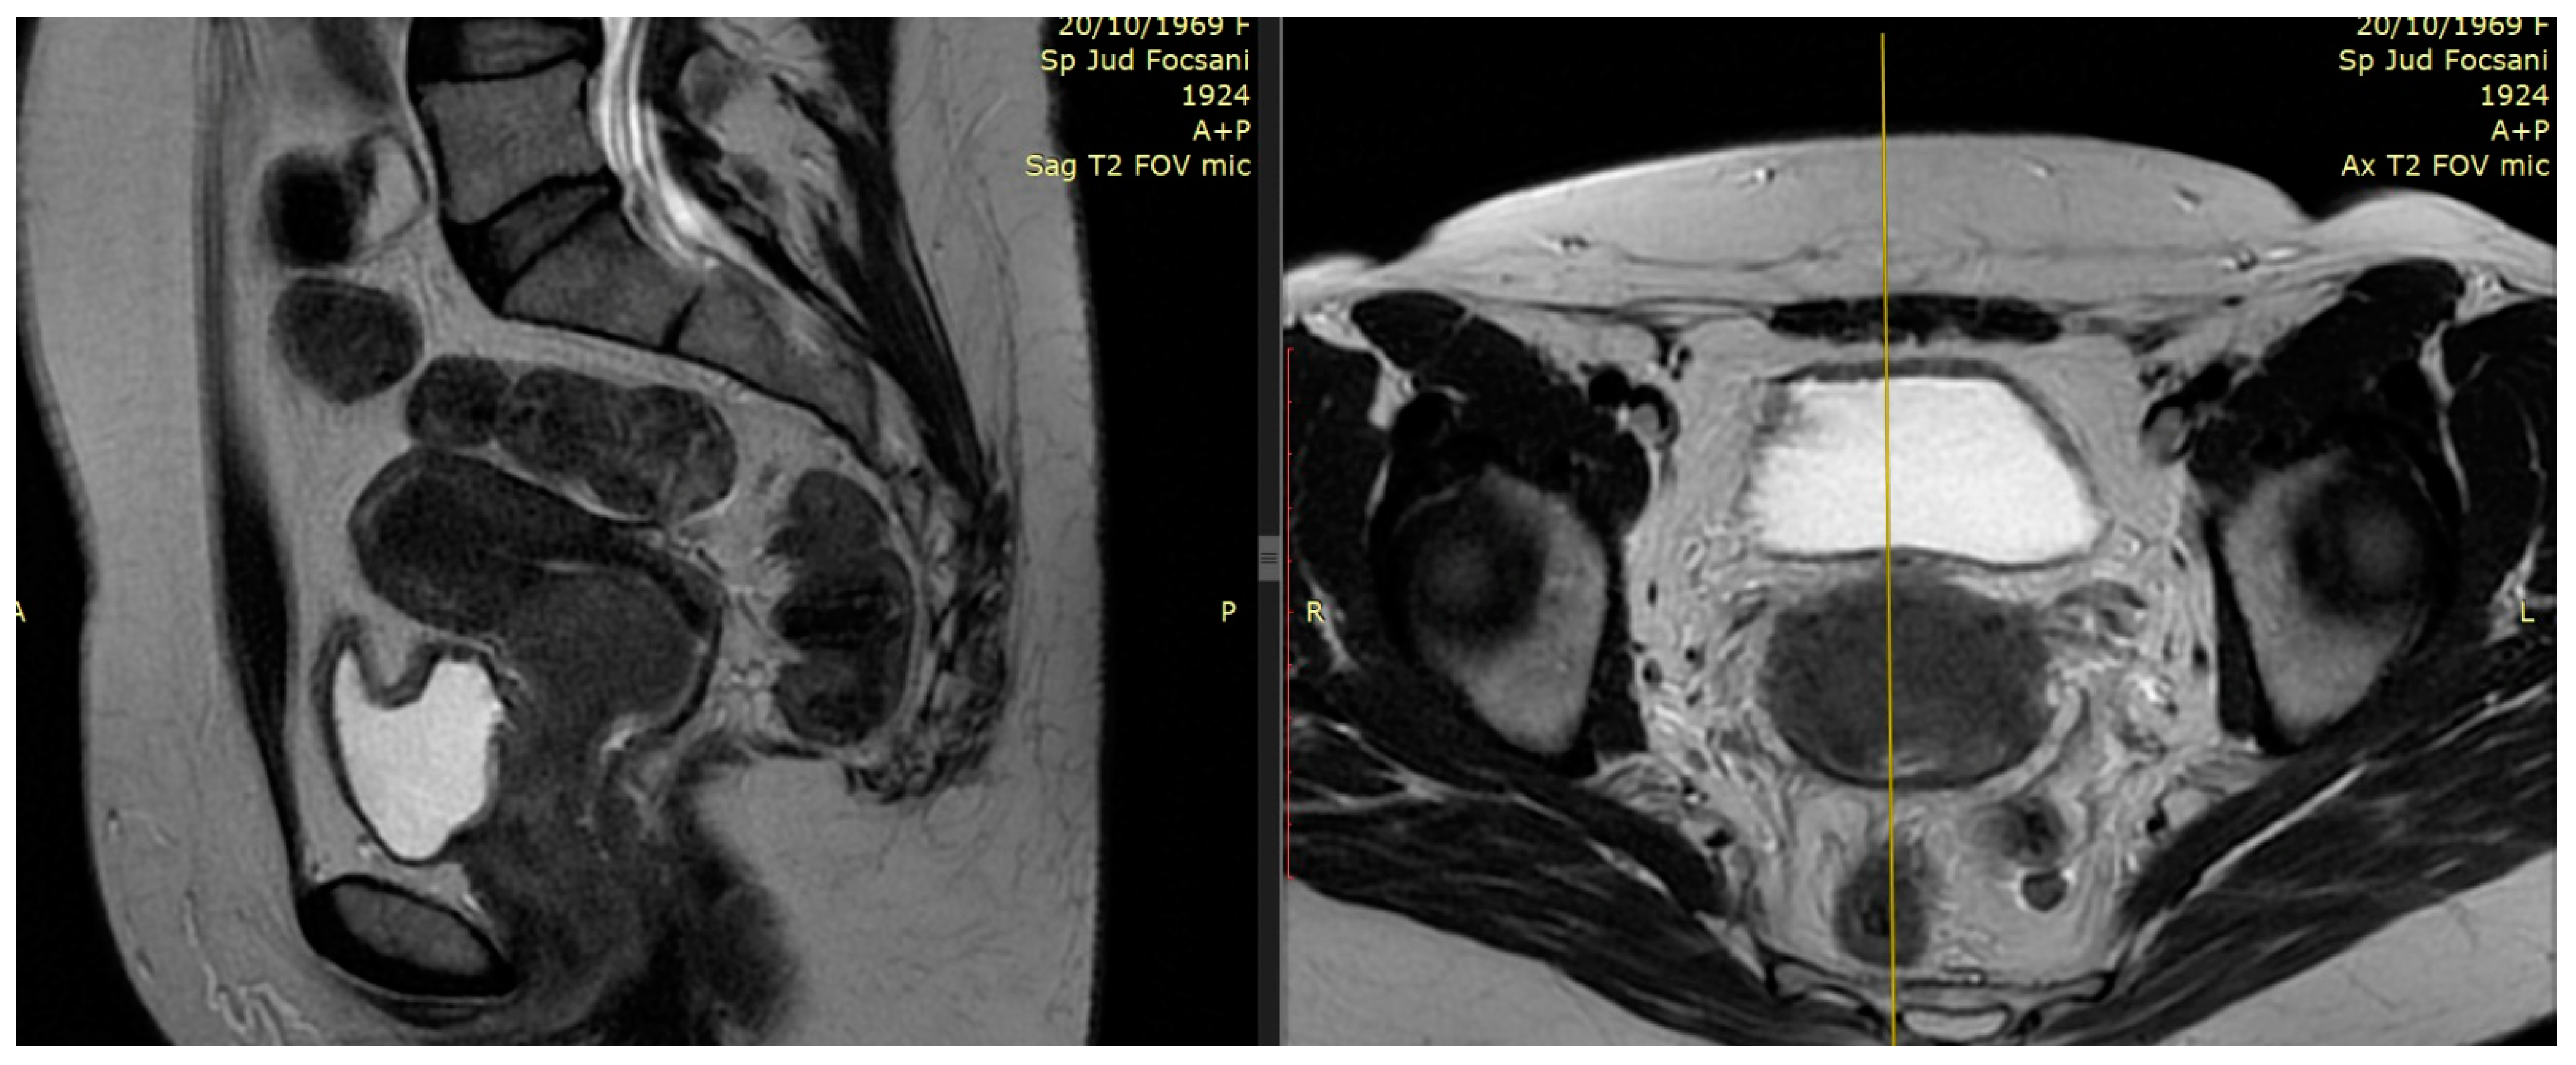

2.1. The Role of MRI